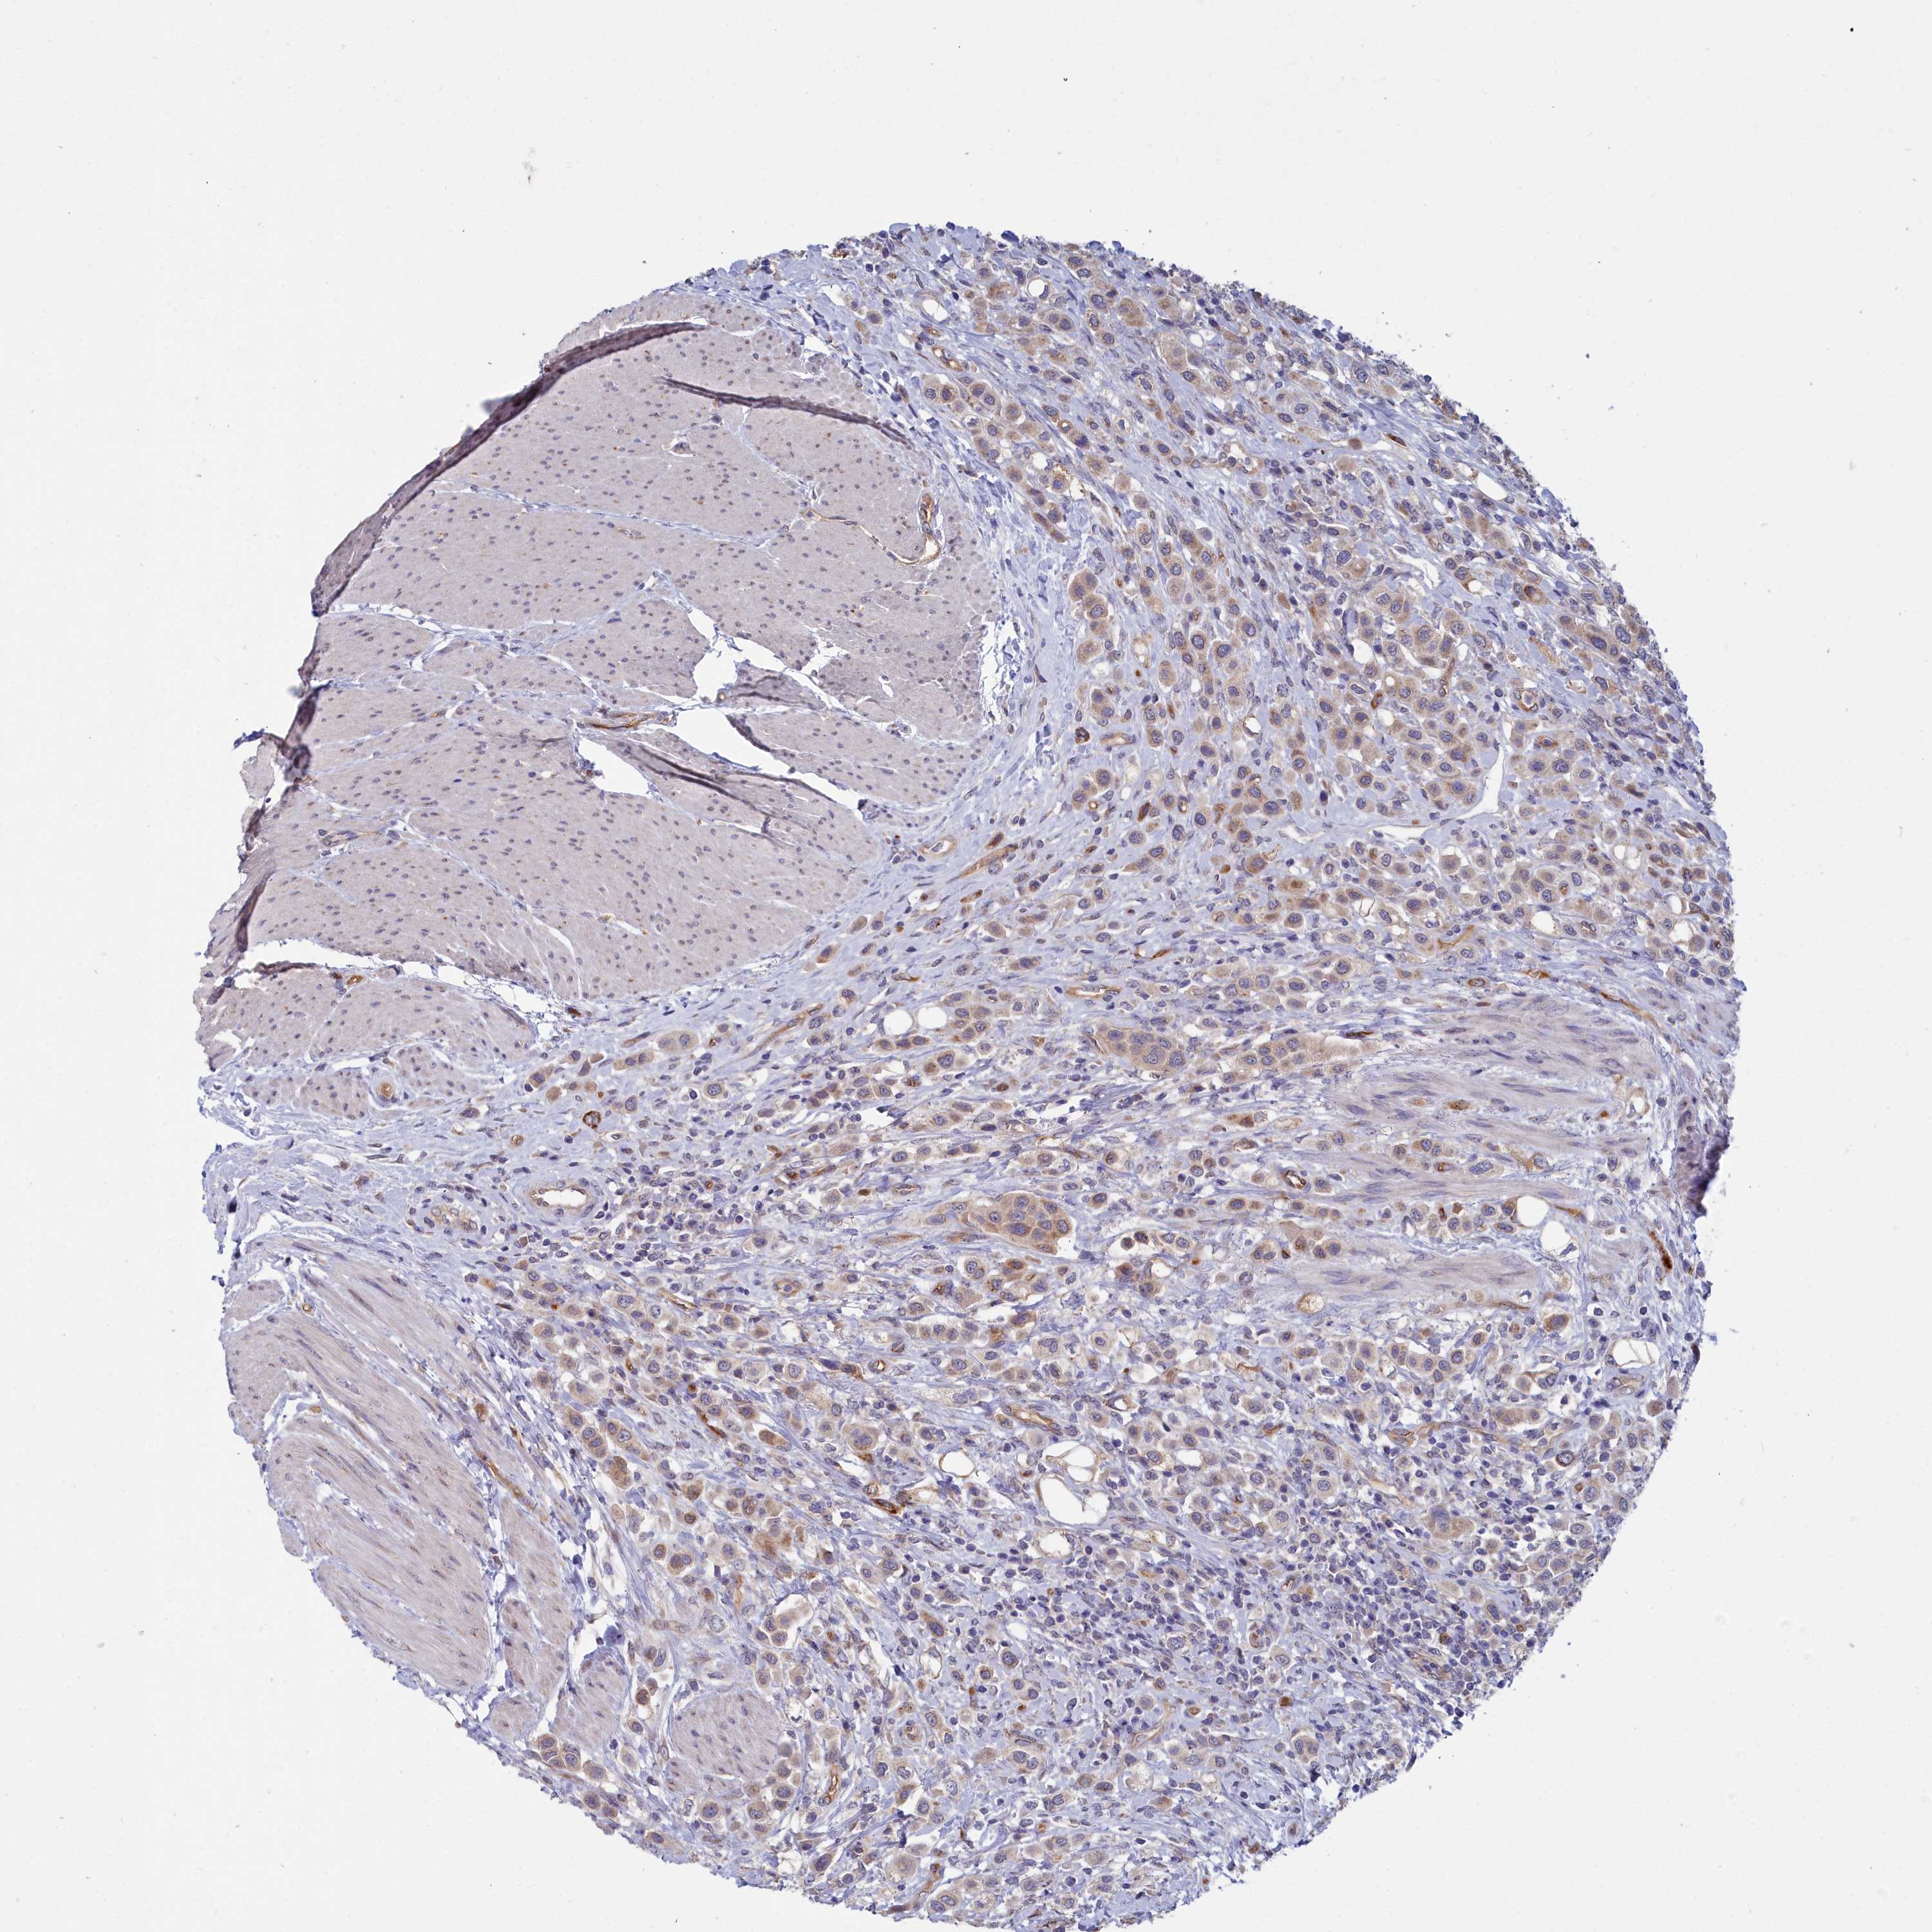

UROTHELIAL CANCER - Protein expressioni

A mouse-over function shows sample information and annotation data. Click on an image to view it in a full screen mode. Samples can be filtered based on level of antibody staining by selecting one or several of the following categories: high, medium, low and not detected. The assay and annotation is described here.

Note that samples used for immunohistochemistry by the Human Protein Atlas do not correspond to samples in the TCGA dataset.

Antibody stainingi

Antibody staining in the annotated cell types in the current human tissue is reported as not detected, low, medium, or high, based on conventional immunohistochemistry profiling in selected tissues. This score is based on the combination of the staining intensity and fraction of stained cells.

Each image is clickable and will lead to virtual microscopy that enables deeper exploration of all samples and also displays staining intensity scores, fraction scores and subcellular localization as well as patient and tissue information for each sample.

Antibody HPA000263

Antibody HPA000763

Antibody CAB037312

Staining

High

Medium

Low

Not detected

Intensity

Strong

Moderate

Weak

Negative

Quantity

>75%

75%-25%

<25%

None

Location

Nuclear

Cytoplasmic/membranous

Cytoplasmic/membranous,nuclear

Urothelial carcinoma, High grade

Urothelial carcinoma, Low grade